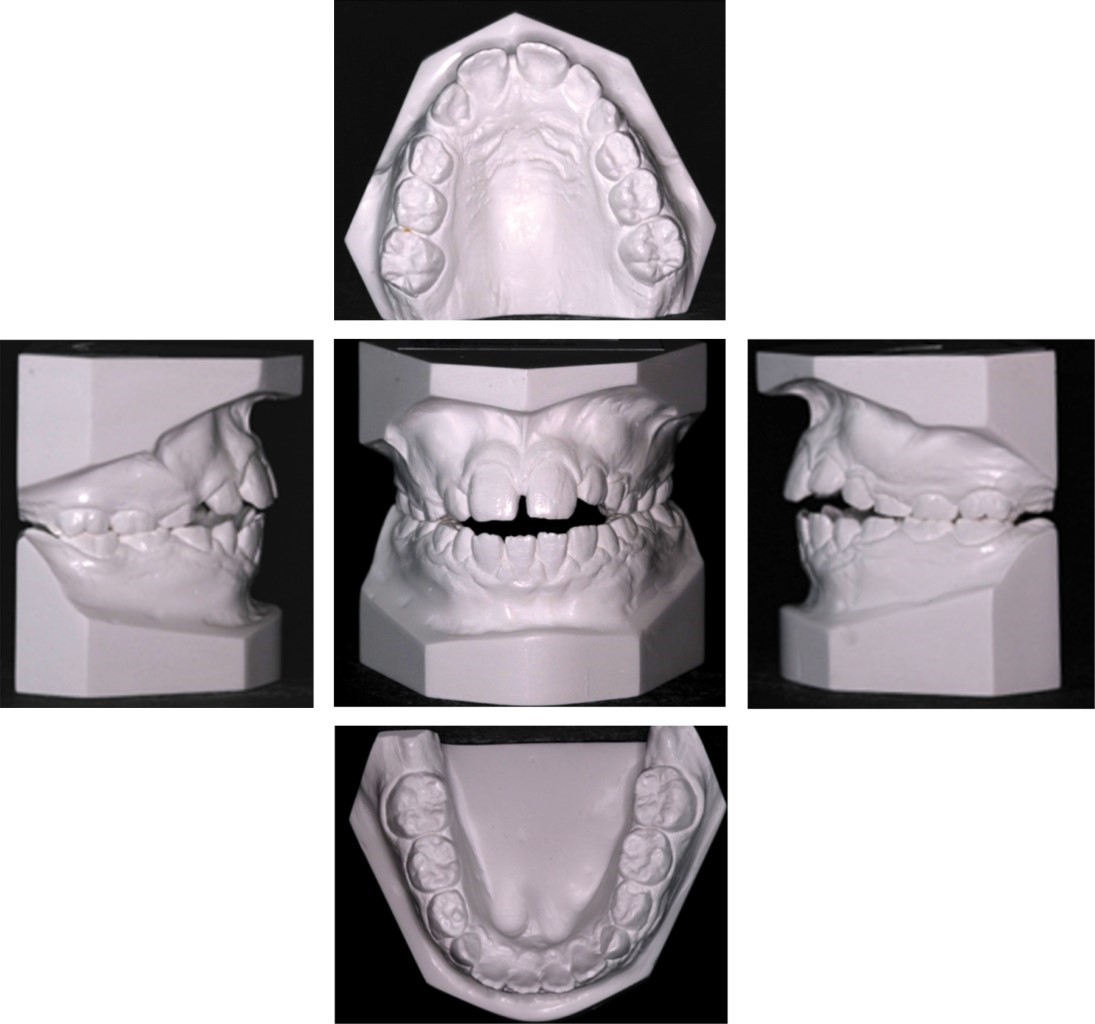

El paciente presenta un biotipo dolicofacial con perfil convexo por crecimiento a favor de las manecillas del reloj, tercios faciales simétricos, labios delgados, frente convexa, proyección del puente nasal recta, buena proyección del tercio medio, posición de la punta nasal alta, ángulo nasolabial abierto, escalón labial recto, poca proyección de pogonión de tejidos blandos, incompetencia labial, la línea media dental no coincide con línea media facial, sonrisa baja, muestra dos dientes en la arcada superior y 10 dientes en la arcada inferior, no muestra corredores bucales, bordes incisales coinciden con línea de sonrisa y no muestra encía al sonreír, como se puede observar en la Figura 1A. En el análisis intraoral, el paciente presenta arcos superior e inferior ovoides, mordida abierta anterior, mordida borde a borde posterior, diastema anterior, líneas medias dentales no coincidentes entre sí, márgenes gingivales superiores e inferiores asimétricos, presencia de piezas temporales, clase III molar izquierda, clase I molar derecha, clase canina bilateral no establecida, overjet de 3 mm, overbite - 4 mm y una curva de Spee de 0 mm, como se muestra en la Figura 1B y Figura 2.

Se mantuvo perfil facial, se logró una sonrisa agradable, se descruzó la mordida posterior; se mejoró notoriamente el overbite inicial de -4 a 2 mm, se obtuvo un correcto overjet, una buena proyección del labio superior, líneas medias centradas, clase I molar y clase I canina bilateral (Figura 7A y B), buen paralelismo radicular (Figura 8A) y sin cambios radicales en sus valores cefalométricos (Figura 8B).

En la Tabla 1 podemos observar los valores cefalométricos iniciales y finales, al final del tratamiento se realizó una comparativa obteniendo excelentes resultados sin alterar por mucho los valores cefalométricos. En la Figura 7A se puede observar cómo a pesar del crecimiento notorio, se mantuvo el perfil facial del paciente, y se logró el cierre de la mordida abierta anterior sin alterar por mucho las inclinaciones de los dientes tanto superiores como inferiores. Por último, en la superposición observamos los cambios dentales y esqueletales del paciente (Figura 8C).

Figura 2